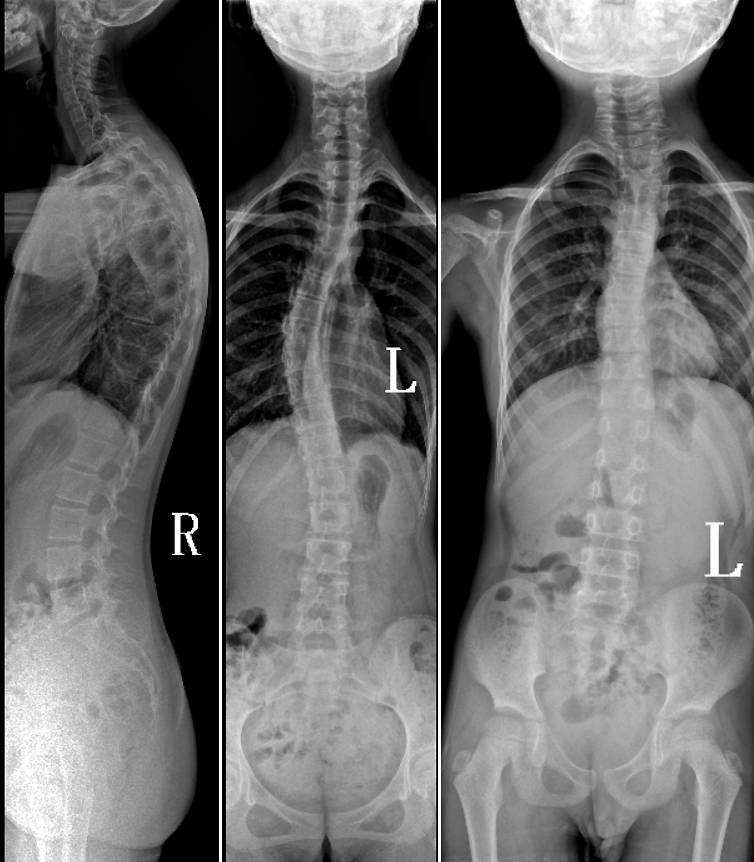

DR是臨床骨科的重要檢查手段之一。在骨科檢查中,脊柱矯形、長骨骨折、腰椎退行性病變等,需要采集脊柱、下肢全景圖像,輔助醫(yī)生臨床診斷,從而制定科學的治療方案,普愛醫(yī)療的大視野平板動態(tài)DR就像是一座橋梁,連接起現(xiàn)代醫(yī)療技術(shù)與當?shù)厝嗣竦尼t(yī)療需求。

普愛醫(yī)療自主研發(fā)的大視野平板動態(tài),采用17"*34"的有效視野,一次曝光即可得到全脊柱或全下肢影像。相較于多張攝影再軟件拼接的DR設備,PLX8600解決了拼接圖像存在密度不均勻,拼接處圖像配準和放大效應等問題,給臨床帶來了真正的大視野影像解決方案。

除了常規(guī)靜態(tài)攝影外,PLX8600的大平板具備動態(tài)透視和點片功能,能夠很好地觀察復雜部位病灶,有效地抓取關鍵幀,降低患者多次攝片的概率。如:全脊柱狀態(tài)評估、長骨關節(jié)活動度、下肢靜脈造影瓣膜功能評估、消化道功能評估、脊髓造影等更多大視野臨床應用,“多面手”都能輕松應對。